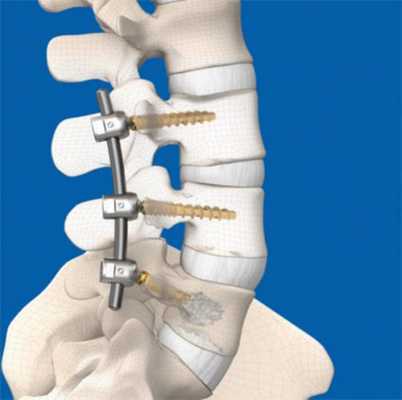

Суть оперативного вмешательства заключается в фиксации поврежденных позвонков с помощью педикул - специальных винтов, которые вживляются в костные ткани и соединяются креплениями, что дает больному шанс на восстановление нормальной работы опорно-двигательного аппарата.

Стандартная фиксация подразумевает использование 4 винтов - 2 устанавливаются в позвонок, который находится выше поврежденного, а еще 2 в нижний позвонок, но иногда используются другие схемы.

Установка конструкции

Второй этап процедуры ТФП - непосредственная установка винтовой системы. Это сложная операция, которая продолжается не менее 2,5-4 часов. Больного укладывают на живот, под тело подкладывают специальные приспособления, чтобы позвоночник находился в нейтральном состоянии, а давление на внутренние органы уменьшилось. После этого под анестезией проводится введение винта на глубину около 80% так, чтобы не затронуть нервные волокна и кровеносную систему. В конце операции стержни крепятся поперечным стабилизатором, и транспедикулярная фиксация считается завершенной.